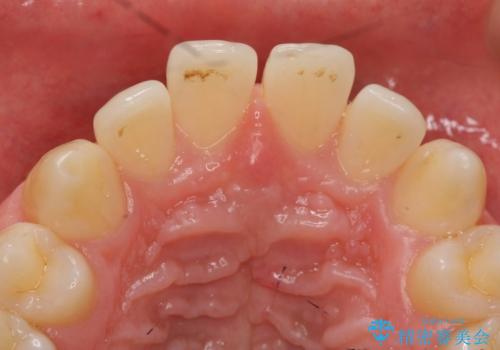

ただし、セラミックは欠ける特性があるため、夜はナイトガードを使用していただくことにしました。

- 天然歯を削ります

- 硬い素材は天然歯を傷つけてしまう場合があります

- かみ合わせや歯ぎしりが強すぎる方はセラミックが割れてしまう可能性があります